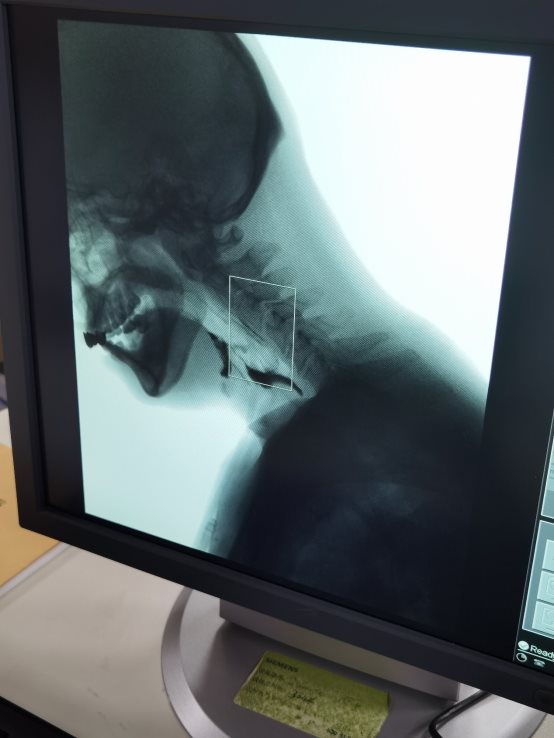

近日,我院康复科二病区联合放射科成功为一位吞咽障碍患者完成了吞咽造影检查(VFSS)。此项技术的开展进一步助力康复评定更加精准。

吞咽造影检查(VFSE),又称电视X线吞咽功能检查(VFSS),是一种通过影像学技术评估吞咽障碍的临床检查方法,在该领域被视为“金标准”。

吞咽造影检查(VFSE)在透视下观察患者吞咽不同黏稠度和容积的、由造影剂包裹的食团,以全面评估整个吞咽过程的不同阶段,包括舌、软腭、咽喉的解剖结构以及食团的运送情况。通过此检查,医生能够观察患者进食各种性状食物时的情况,包括吞咽的启动,是否有误吸以及误吸后的清除能力,进而发现吞咽障碍的结构性或功能性异常的病因、部位、程度和代偿情况。这些信息对于选择有效的治疗措施、观察治疗效果以及判断是否拔除鼻饲管、胃造瘘管等都具有重要意义。